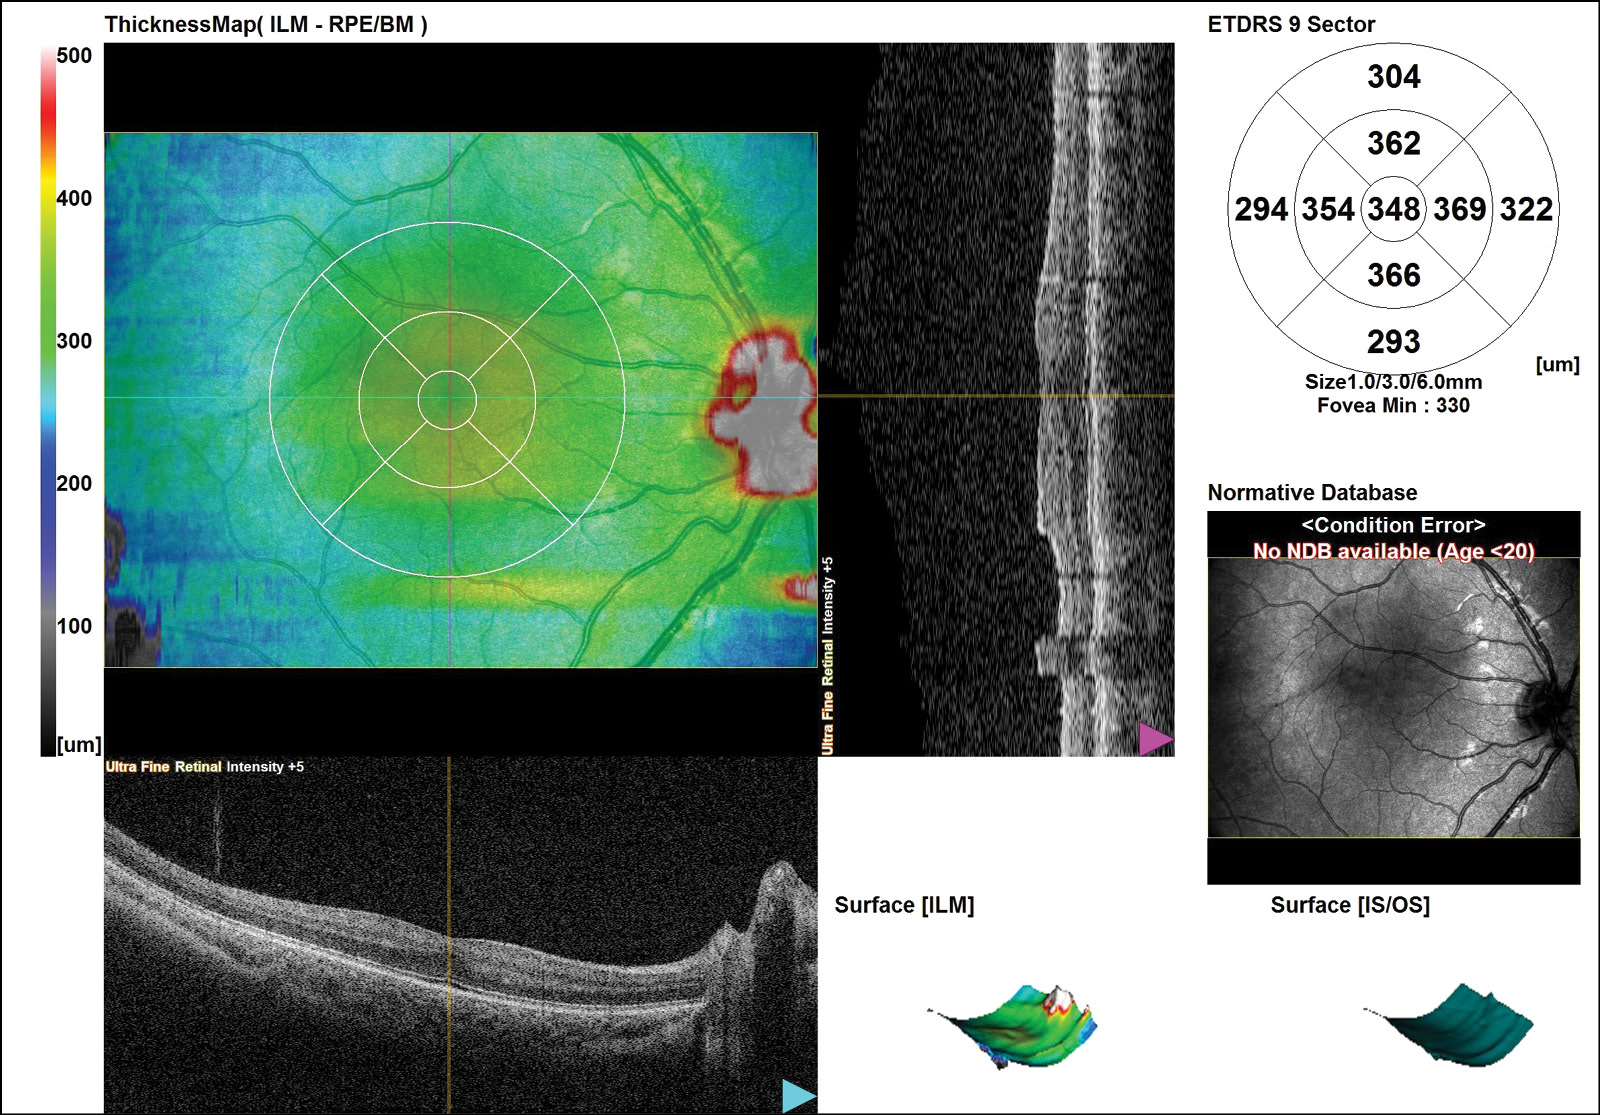

Сглаженность или отсутствие фовеолярной депрессии по данным ОКТ наблюдалось на 14 глазах, в том числе на 3 глазах с I степенью РН, на 5 глазах — с заболеванием II степени, а на 6 глазах — с III степенью РН. Отсутствие или сглаженность фовеолярной депрессии на глазах с заболеванием I–II степеней в большинстве случаев объяснялось сохранением эмбрионального строения макулы (нарушение дифференцировки макулы) (рис. 1).

Рис. 1. Оптическая когеренная томография макулярной зоны сетчатки ребёнка с диагнозом: РН, I cтепень, рубцовая фаза: персистенция внутренних слоёв сетчатки в фовеа.